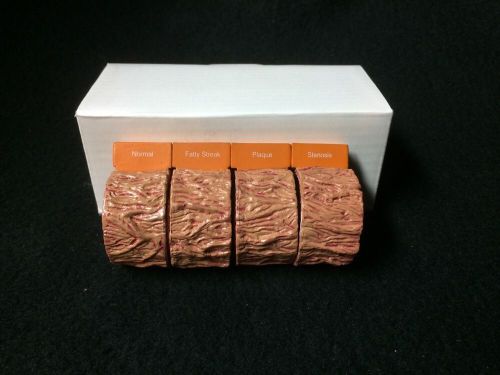

Artery Red Blood Cells Anatomical Model Pathology

GPI #2650 - 4 Piece Artery Anatomical Model (NEW)